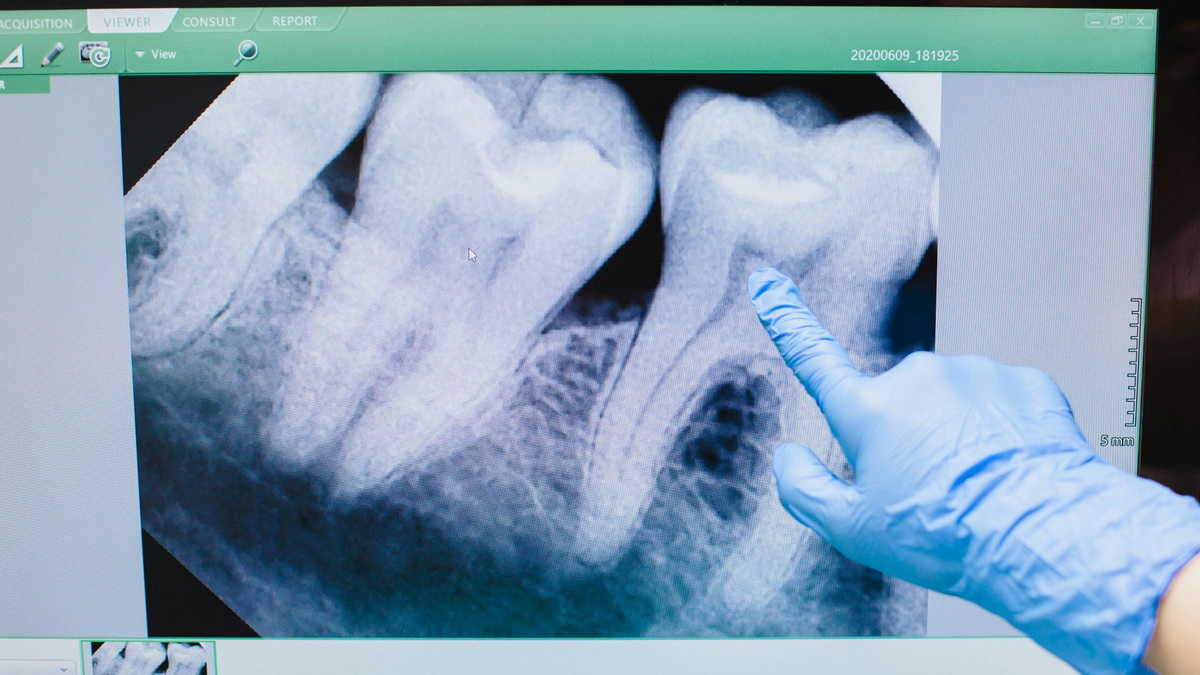

Diese Positionen werden in der Regel durch Panoramaröntgen oder eine zahnärztliche Tomographie (3D-Bildgebung) eindeutig bestimmt. Entsprechend werden die Behandlungsentscheidungen getroffen. In den Jimer Dental Clinics verwenden wir unsere modernen Panoramaröntgen- und Dentaltomographiegeräte (3D-Bildgebung), um eine detaillierte Visualisierung der Weisheitszähne im Knochen und ihrer Nähe zu den Nachbarzähnen zu ermöglichen und so eine wirksame Diagnose und Behandlung zu ermöglichen.

Drücken diese retinierten Zähne auf Nachbarzähne und liegen in der Nähe des Kiefernervs, müssen sie von einem Kieferchirurgen operativ entfernt werden, um Probleme zu vermeiden. Während der Weisheitszahnentfernung in den Jimer Dental Clinics erfolgt eine detaillierte Untersuchung und Diagnose mithilfe modernster Bildgebungsverfahren wie der 3D-Volumentomographie (CBCT) und Panoramaröntgen. Anhand radiologischer Bilder beurteilt der Kieferchirurg die Position des Zahns im Kieferknochen, seine Nähe zu den Nerven und Nachbarzähnen millimetergenau und erstellt anschließend den Operationsplan. Die Operationsplanung, insbesondere bei teilweise oder vollständig retinierten Weisheitszähnen, wird dank dieser fortschrittlichen Bildgebung deutlich sicherer.

Zuerst werden die Lage des Zahns, sein Abstand zum umliegenden Gewebe und seine Beziehung zu den Nerven gründlich untersucht. Es wird eine Panorama-Röntgenaufnahme oder, falls erforderlich, eine zahnärztliche Computertomographie (CT) angefertigt. Der Kieferchirurg wertet anschließend alle Bilder aus und erstellt einen Plan, der entscheidet, ob der Zahn durch einfache Extraktion oder chirurgische Entfernung entfernt wird.

Das für die Heilung in der Extraktionshöhle nach einer Zahnextraktion notwendige Blutgerinnsel kann sich möglicherweise nicht wie erwartet oder gar nicht bilden. Dies kann zur Freilegung des Knochens und damit zu einer Komplikation namens Alveolitis sicca (trockene Alveole) führen. Darüber hinaus kann sich bei unzureichender Mundhygiene nach der chirurgischen Extraktion und häufigem Rauchen eine Infektion an der Wundstelle entwickeln. Patienten wird daher empfohlen, auf Mundhygiene zu achten und mit dem Rauchen aufzuhören. Bei Weisheitszähnen im Unterkiefer kann es aufgrund ihrer Nähe zum Nerv zu Nervenschäden kommen. Um dies zu verhindern, sollte der Eingriff sorgfältig geplant und eine CT-Untersuchung durchgeführt werden. Risiken sollten im Vorfeld durch bildgebende Verfahren identifiziert, Vorsichtsmaßnahmen getroffen und die Extraktion fachgerecht von einem Kieferchirurgen durchgeführt werden.

In den Jimer Dental Clinics führen unsere auf Kieferchirurgie spezialisierten Kieferchirurgen vor der Weisheitszahnentfernung eine detaillierte radiologische Untersuchung (Panoramaröntgen und gegebenenfalls 3D-Volumentomographie) sowie eine umfassende intraorale Untersuchung durch und analysieren dabei alle Risiken sorgfältig. Auf diese Weise versuchen wir, potenziellen Komplikationen wie Nervenschäden, Infektionen und einer trockenen Alveole vorzubeugen. Die chirurgische Entfernung eines Weisheitszahns durch einen Kieferchirurgen minimiert diese potenziellen Risiken weitgehend.